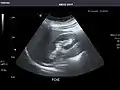

Renal ultrasonography

Ultrasound scan of a kidney (right side)

Ultrasonography of the kidneys is essential in the diagnosis and management of kidney-related diseases. The kidneys are easily examined, and most pathological changes in the kidneys are distinguishable with ultrasound.[7]